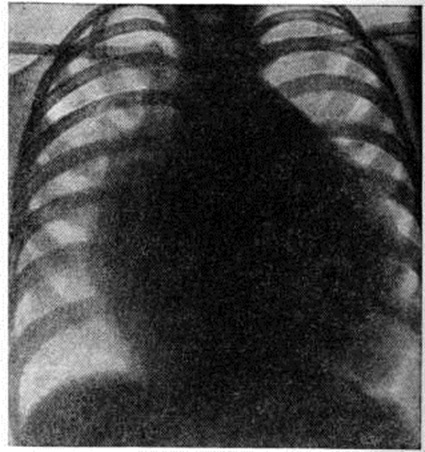

Послеоперационная летальность до 7%. Более чем у половины оперированных сохраняется слабый систолический шум вследствие незначительной регургитации из желудочка. Ок. 80% пациентов в отдалённые сроки после операции практически здоровы. Атриовентрикулярный канал (полная форма). Полный атриовентрикулярный канал (рисунок 6) — сложный Пороки сердца врождённые, при котором, кроме первичного дефекта межпредсердной перегородки и расщепления створок клапанов, имеется и дефект межжелудочковой перегородки, создающий с дефектом межпредсердной перегородки единое отверстие. Этот порок характеризуется преимущественно аномалиями створок клапанов, наличием общего атриовентрикулярного отверстия и подстворочного дефекта различных размеров в межжелудочковой перегородке (рисунок 1, г). Очень редко дефект межпредсердной перегородки закрывается, а аномалия представляет собой сочетание расщепления створки с дефектом межжелудочковой перегородки. Крайняя форма полного атриовентрикулярного канала — большой первичный дефект межпредсердной перегородки, переходящий в большой дефект межжелудочковой перегородки, и единый атриовентрикулярный клапан, в котором половинки правого и левого предсердно-желудочковых клапанов срастаются настолько, что представляют собой переднюю и заднюю створки. При полном атриовентрикулярном канале хорды аномальных створок могут перебрасываться в смежный желудочек, прикрепляться к одной сосочковой мышце. Нарушение гемодинамики обусловлено регургитацией крови из желудочков в предсердия и артериовенозным шунтированием через патологический отверстие в перегородках сердца. При полном атриовентрикулярном канале сердечная недостаточность проявляется уже в первые недели или месяцы жизни. Дети плохо развиваются физически, часто страдают инфекционные болезнями. Возникает одышка (даже в покое), резкая утомляемость, печень и сердце увеличиваются. Выслушивается пансистолический шум над верхушкой сердца и по левому краю грудины. При физических нагрузках появляется лёгкий цианоз. Определяемое расщепление II тона с усилением лёгочного компонента связано с гиперволемией малого круга и блокадой правой ножки пучка Гиса. На ЭКГ — отклонение электрической оси сердца влево. На ФКГ над верхушкой сердца и в четвёртом межреберье слева регистрируется интенсивный систолический шум, связанный с регургитацией крови из желудочков и сбросом крови из левого желудочка в правый. Эхокардиограмма регистрирует необычные движения передней створки митрального клапана, иногда её расщепление и наличие промежутка между ней и межжелудочковой перегородкой. Рентгенологически определяется умеренная или значительная кардиомегалия и дилатация лёгочного ствола (рисунок 7). При катетеризации сердца катетер легко проникает во все его отделы. В правом предсердии обнаруживается артериальная кровь, давление в нем и лёгочном стволе повышено. Отмечается высокое сопротивление лёгочных сосудов. При рентгеноконтрастном исследовании определяется деформация митрального клапана, попадание контрастного вещества в правые отделы сердца, левое предсердие, а также деформация выходного отдела левого желудочка. Лечение лёгочной гипертензии в раннем детском возрасте оперативное: сужение лёгочного ствола; эта паллиативная операция не всегда даёт положительный результат. Радикальная операция, проводимая в условиях искусственного кровообращения, направлена на закрытие дефекта заплатой и восстановление обоих предсердно-желудочковых клапанов. Для проведения коррекции иногда приходится рассекать обе (переднюю и заднюю) створки, чтобы вшить заплату, после чего противолежащие половинки створок фиксируют к заплате и между собой. В тех случаях, когда сухожильные хорды клапана перекидываются в соседний желудочек, для них в заплате оставляют маленькое отверстие или производят иссечение клапана и их протезирование. Большинство больных с полным атриовентрикулярным каналом погибают в раннем детском возрасте. У выживших развивается сердечная недостаточность, лёгочная гипертензия, часто возникают респираторные заболевания. После операций главная причина летальных исходов (около 20%) — неадекватная коррекция порока (сохранение регургитации, сброса крови или сердечная недостаточность в результате необратимости лёгочной гипертензии). У выживших практически всегда выслушивается систолический шум, связанный с небольшой регургитацией. В отдалённые сроки после операции погибает около 10% больных, нередко отмечается остаточная недостаточность либо стеноз митрального или трикуспидального клапана, у 5—10% — полная атриовентрикулярная блокада. Большинство больных чувствуют себя лучше, чем до операции,— уменьшается одышка, они становятся более толерантными к физическим нагрузкам. Уменьшаются размеры сердца и кровенаполнение сосудов лёгких. Гипоплазия правого желудочка обычно сочетается с атрезией лёгочного ствола, его стенозом и атрезией трёхстворчатого клапана. Очень редко порок бывает изолированным. Он является разновидностью аномалии развития правых отделов сердца (трикуспидальной атрезии, аномалии Эбштейна, стеноза и атрезии лёгочного ствола, тетрады Фалло). Наблюдаются две его морфологический формы: правый желудочек с небольшой полостью, резко гипертрофированной стенкой и изменённым трикуспидальным клапаном; правый желудочек с большой полостью, тонкими фиброзно-перерождёнными стенками и неполноценным трёхстворчатым клапаном. Показано наложение кавопульмонального или аортолёгочного анастомоза. Дефекты венозного синуса. При этом Пороки сердца врождённые дефект межпредсердной перегородки локализуется сверху или снизу (полая вена переходит в стенку левого предсердия) и вены лёгкого впадают в верхнюю (нижнюю) полую вену или её устье. Чаще встречаются верхние дефекты венозного синуса. Верхняя полая вена ниже впадения непарной вены значительно расширяется. В неё двумя-тремя стволами вливаются вены верхней доли правого лёгкого, а вены средней доли — в устье полой вены на уровне дефекта перегородки. При нижнем дефекте венозного синуса отмечается транспозиция нижней лёгочной вены вправо, благодаря чему иногда создаётся видимость смещения нижней полой вены в сторону левого предсердия. Отсутствие перегородки между полыми венами со смещением лёгочных вен вправо называют средним дефектом венозного синуса. Размеры дефекта перегородки — от 0,5 до 2 сантиметров. При нижнем дефекте венозного синуса устье нижней лёгочной вены смещено вправо. Клапан нижней полой вены (евстахиева заслонка) иногда, сливаясь с межпредсердной перегородкой в области коронарного синуса, создаёт условия для тока крови из этой вены в левое предсердие. Задняя стенка нижней полой вены переходит в стенку левого предсердия. Нарушения гемодинамики аналогичны тем, которые наблюдаются при вторичном дефекте межпредсердной перегородки. Нижний дефект венозного синуса иногда создаёт условия для направления струи крови из нижней полой вены в левое предсердие. Небольшой венозно-артериальный сброс приводит к появлению слабого цианоза и может быть причиной парадоксальной эмболии (попадания венозного тромба в артерии большого круга кровообращения). Эмболия и абсцессы мозга, инфаркты почек и другие осложнения — следствие парадоксальной эмболии. При транспозиции лёгочных вен кровоток в соответствующей части лёгочной ткани усилен (давление в правом предсердии ниже, чем в левом), что сказывается при физических нагрузках. Эффективный газообмен нарастает слабо из-за увеличения балластно-циркулирующей крови. Клиническая картина характеризуется теми же признаками, что и при вторичном дефекте межпредсердной перегородки. Данные ЭКГ, ФКГ и рентгенологическое исследования аналогичны таковым при дефекте межпредсердной перегородки. Однако аномальное впадение лёгочных вен в верхнюю полую вену рентгенологически можно заподозрить по необычно высоко расположенному корню правого лёгкого на фоне усиления прикорневого рисунка. При катетеризации сердца катетер проводят в аномальную лёгочную вену и через дефект в межпредсердной перегородке — в левое предсердие. В тех случаях, когда катетер провести не удаётся, применяют транссептальную пункцию с введением контрастного вещества в левое предсердие. Для распознавания места впадения лёгочных вен также производят их контрастирование. Направление движения контрастного вещества выявляет нормальное или аномальное впадение лёгочных вен. Лечение оперативное. Дефект венозного синуса устраняют либо на «открытом» сердце с помощью заплаты (рисунок 8) или пластики межпредсердной перегородки и задней стенки верхней полой вены, которые подшивают к правому краю аномальных лёгочных вен, либо на работающем сердце путём разделения расширенной верхней полой вены на два канала с последующим подшиванием места деления к нижнему краю дефекта. В последнем случае после коррекции отток легочно-венозной крови осуществляется через сформированный канал верхней полой вены и дефект межпредсердной перегородки в левое предсердие. Послеоперационная летальность около 1%; в 3—5% случаев наблюдается реканализация дефекта. Отдалённые результаты — 80—90% прооперированных практически здоровы. Дефект межжелудочковой перегородки. Изолированный дефект межжелудочковой перегородки — наиболее частый Пороки сердца врождённые у новорождённых (30—40%). Клинические, признаки порока были описаны П. Ф. Толочиновым в 1874 год и Роже (Н. L. Roger) в 1879 год (Толочинова—Роже болезнь). Нарушения формирования межжелудочковой перегородки возникают в первые три месяца беременности. Приблизительно в 85% случаев дефекты располагаются в перепончатой части межжелудочковой перегородки (рисунок 9 и 1, д), то есть непосредственно под правой коронарной и некоронарной створками клапанов аорты (со стороны левого желудочка), на месте перехода передней в перегородочную створку трёхстворчатого клапана под медиальным рогом наджелудочкового гребня межжелудочковой перегородки (со стороны правого желудочка). Иногда дефекты локализуются непосредственно под правой и частично левой полулунными заслонками клапанов аорты (слева), выше наджелудочков ого гребня под клапаном лёгочного ствола (справа). Чаще отверстия располагаются непосредственно под некоронарной створкой клапанов аорты (слева) и под перегородочной створкой трёхстворчатого клапана (справа) вдоль его фиброзного кольца. Ок. 2% случаев — это мышечная локализация дефектов; при этом могут быть и множественные отверстия. Очень редко наблюдается комбинация мышечной и иной локализации дефекта перегородки. Диаметр дефектов перепончатой части межжелудочковой перегородки варьирует от нескольких миллиметров до 3 см; в основном они круглой или овальной формы. Надгребневые дефекты по величине, как правило, средние и большие (от 7 миллиметров до 2 сантиметров) и также круглые; примыкающие к клапанам аорты и лёгочного ствола — более сложной формы. Дефекты вблизи трёхстворчатого клапана, расположенные вдоль его фиброзного кольца, имеют размеры от нескольких миллиметров до 3—4 сантиметров, форма их различна — от круглой до продольной, от полулунной до треугольной. Мышечные дефекты обычно круглые и небольшие. В кардиохирургии размеры дефекта определяются их отношением к диаметру аорты (средние по величине дефекты имеют в диаметре от ¼ до ½ диаметра аорты). Самые большие дефекты простираются от наджелудочкового гребня вниз и кзади вдоль фиброзного кольца под перегородочную и даже заднюю створки трёхстворчатого клапана. Иногда полностью отсутствует верхняя часть межжелудочковой перегородки и аорта открывается как бы в оба желудочка. Края маленьких дефектов обычно покрыты фиброзной тканью, средних и больших — мышечной (там, где отверстие не примыкает к устью клапанов). Проводящая система сердца (смотри полный свод знаний) — пучок Гиса и его ножки — при высоких подгребневых дефектах проходит по нижнезаднему краю дефекта под эндокардом (со стороны левого желудочка); при задних подстворочных дефектах расположение пучка непостоянное — либо по задне-верхнему, либо по задненижнему краю отверстия. При непосредственной близости средних и больших дефектов к фиброзному кольцу клапанов аорты из-за отсутствия достаточной опоры возникает недостаточность клапанов. Так, при локализации дефекта в перепончатой части перегородки или над наджелудочковым гребнем может возникнуть пролабирование полулунной заслонки клапанов аорты в полость правого желудочка с появлением аортальной регургитации различной степени. В некоторых случаях существование артериовенозного сброса рано приводит к гипертрофии правого желудочка, преимущественно его выходного отдела. Увеличение массы наджелудочкового гребня и передней стенки желудочка формирует подклапанное сужение лёгочного ствола, которое проявляется в момент сокращения желудочка (т. е. в систолу). Градиент давления между входным и выходным отделами желудочка может возрасти настолько, что давление в правом желудочке вначале становится равным давлению в левом, а потом начинает его превышать. Спонтанное закрытие дефекта перегородки благодаря разрастанию фиброзной ткани и рубцеванию, а также прирастание створок трёхстворчатого клапана или клапанов аорты к краям дефекта происходит у 25—50% больных, преимущественно в раннем детском возрасте. Дефект межжелудочковой перегородки может сочетаться с артериальным протоком, дефектом межпредсердной перегородки, коарктацией аорты, врождённым митральным стенозом или митральной недостаточностью, аномальной левой верхней полой веной, впадающей в коронарный синус. Направление и величина шунта на уровне желудочков исключительно зависят от соотношения давления между желудочками в систолу и диастолу. При небольшом и среднего размера дефекте движущей силой шунта является градиент давления между левым и правым желудочками. В этом случае объем сбрасываемой крови будет определяться величиной сопротивления, создаваемого патологический отверстием. Максимальная разница в давлении падает на середину и вторую половину систолы. В эту фазу сокращения возникает наиболее интенсивный кровоток через дефект, что определяет на ФКГ характерную форму систолического шума (с усилением ко II тону). При большом дефекте сопротивление не создаётся. Градиент между желудочками, как правило, невелик. Величина шунта в этом случае зависит только от соотношения сосудистого сопротивления в большом и малом круге кровообращения. Преимущественный кровоток будет в сторону меньшего сопротивления. Кроме того, в систоле происходит сокращение перегородки и соответственно меняются размеры и форма дефекта, его соотношение с внутриполостными структурами (клапанами) и наджелудочковым гребнем, что также влияет на величину шунта. В диастоле и в самом начале систолы направление и величина сброса крови определяются относительной податливостью (эластичностью) желудочковых отделов, диастолическим давлением, асинхронностью сокращений. Артериовенозное шунтирование приводит к возрастанию лёгочного кровотока. Через левое атриовентрикулярное отверстие протекает увеличенное количество крови. В результате возникает перегрузка обоих желудочков и левого предсердия, которая соответствует величине шунта (слева направо). При развитии лёгочной гипертензии объем шунта уменьшается, а позднее, когда давление в правом желудочке начинает превышать давление в левом желудочке, становится преимущественно венозно-артериальным. На этой стадии дилатация левых отделов сердца несколько уменьшается, а правый желудочек резко гипертрофируется. Артериовенозный шунт при дефекте межжелудочковой перегородки оказывает существенное влияние на сосуды малого круга кровообращения. При малом дефекте давление в правом желудочке не повышено, несколько увеличен лёгочный кровоток: на этой стадии легочно-сосудистое сопротивление нормальное. При большом дефекте перегородки оно может быть увеличено, что приводит к развитию лёгочной гипертензии. Объем шунта и соответственно лёгочный кровоток обратно пропорциональны соотношению величин сопротивления в малом и большом кругах кровообращения. Так, например, при отношении менее 0,4 артериовенозный сброс крови может быть большим, а лёгочный кровоток резко увеличенным, что приводит к лёгочной гипертензии гиперволемического характера; если отношение колеблется между 0,4 и 0,7, лёгочный кровоток умеренно увеличен, а лёгочная гипертензия будет смешанного характера — гиперволемическая (т. е. сохранен сброс крови) и гиперкинетическая (т. к. повышено легочно-сосудистое сопротивление). Отношение более 0,7 соответствует уравновешенному или обратному сбросу крови, высокому лёгочному артериальному давлению и уменьшенному лёгочному кровотоку; лёгочная гипертензия гиперкинетическая. Если у здоровых людей физическая нагрузка, сопровождающаяся заметным повышением производительности сердца, приводит к падению легочно-сосудистого сопротивления, то при наличии фиксированного высокого лёгочного сопротивления повышение нагрузки может привести к острой сердечной недостаточности. У больных с дефектом межжелудочковой перегородки и высокой лёгочной гипертензией увеличение минутного объёма сердца означает увеличение венозно-артериального сброса, усиление цианоза и ещё большую потребность в артериальной крови. У большинства больных при небольшом дефекте межжелудочковой перегородки и незначительном артериовенозном шунте клинические, проявлений порока практически не отмечается. При больших дефектах перегородки (в 20% случаев) наблюдается выраженная клинические, картина. У новорождённых при большом дефекте перегородки и высоком легочно-сосудистом сопротивлении быстро возникает острая сердечная недостаточность, которая может стать хронической; наблюдается физическое недоразвитие. У новорождённых с эмбриональным типом сосудов, высоким сосудистым сопротивлением, гиперкинетической лёгочной гипертензией, являющихся необратимыми, превышением давления в правом желудочке по сравнению с левым наступает венозно-артериальный сброс крови, приводящий к появлению цианоза и эритроцитоза (смотри полный свод знаний). Такое сочетание гемодинамических и клинические, изменений, развивающихся при дефекте межжелудочковой перегородки, носит название комплекса Эйзенменгера. Новорожденные с большим дефектом перегородки, незначительно увеличенным легочно-сосудистым сопротивлением и лёгочной гипертензией гиперволемического характера также отстают в физическом развитии и плохо переносят физические нагрузки. Если на протяжении первых лет жизни не происходит спонтанного закрытия дефекта или его уменьшения, то к 20 годам лёгочная гипертензия становится гиперкинетической и необратимой, развивается комплекс Эйзенменгера. Появляются вначале при нагрузках, позднее постоянно цианоз, эритроцитоз, венозно-артериальный шунт. В некоторых случаях легочно-сосудистое сопротивление не повышается и наблюдается хронический сердечная недостаточность. У части больных развивается бактериальный эндокардит (смотри полный свод знаний). Таким образом, клинические, картина порока имеет прямую зависимость от размеров дефекта перегородки, величины лёгочного кровотока и степени лёгочной гипертензии. При небольшом дефекте перегородки над сердцем в третьем-четвёртом межреберье по левому краю грудины наблюдается дрожание и выслушивается интенсивный систолический шум, хотя со стороны больного жалобы отсутствуют. Дети со средним и большим дефектом перегородки часто жалуются на одышку при умеренных физических нагрузках и повышенную утомляемость. При физикальном обследовании выявляется увеличенное сердце, отчётливое дрожание и выраженный пансистолический шум с максимумом в четвёртом межреберье по левому краю грудины. Верхушечный толчок усилен. Над верхушкой сердца — лёгкий протодиастолический шум. II тон расщеплен (при отсутствии лёгочной гипертензии), его лёгочный компонент может быть усилен. У больных с аортальной недостаточностью (вследствие пролабирования створки клапанов аорты) прослушивается протодиастолический шум над аортой в третьем-четвёртом межреберье слева от грудины. Нередко имеются признаки сердечной недостаточности (тахикардия, одышка, гепатомегалия, отеки), которую усиливают сопутствующие Пороки сердца врождённые Присоединяются нарушения сердечного ритма. При декомпенсации несколько ослабевают систолический шум и II тон. Для больных с крайней степенью лёгочной гипертензии характерен слабый систолический шум и резко усиленный монофазный тон. На ЭКГ отмечаются признаки левожелудочковой гипертрофии. При большом артериовенозном шунте и развитии лёгочной гипертензии оба желудочка гипертрофированы. С нарастанием лёгочной гипертензии увеличиваются зубцы R в правых прекардиальных отведениях. При комплексе Эйзенменгера — картина выраженной систолической перегрузки правого желудочка. При рентгенологическое исследовании у больных со средними и большими дефектами перегородки находят увеличение обоих желудочков, усиление лёгочного рисунка в прикорневых отделах лёгких и расширение тени лёгочных сосудов (рисунок 10). С развитием лёгочной гипертензии размеры сердца несколько сокращаются, начинает выбухать дуга лёгочного ствола, ослабляется периферический лёгочный рисунок, резко гипертрофирован и увеличен правый желудочек. При катетеризации сердца катетер нередко удаётся провести из правого желудочка через дефект межжелудочковой перегородки в аорту. Измерение давления в правых отделах сердца и лёгочном стволе позволяет оценить степень и обратимость нарушений гемодинамики. Сброс крови через межжелудочковый дефект устанавливают либо исследованием крови на насыщение кислородом, либо красочными, термодилюционными, платиноводородными пробами. Дефект перегородки обнаруживается при контрастировании левого желудочка. Для этого катетер проводят ретроградно по Сельдингеру в корень аорты. Подтягивают проволочный проводник на несколько сантиметров, благодаря чему конец зонда становится менее упругим и его изгибают. После этого катетер благодаря наличию кривизны располагается по центру аорты и сравнительно легко проводится в полость левого желудочка. Этот момент может сопровождаться появлением групповых экстрасистол. Рентгеноконтрастное исследование предпочтительно выполнить в левой косой или боковой проекциях. Через катетер в полость левого желудочка с помощью автоматического шприца под давлением 1 ½—2 атмосфер в течение нескольких секунд вводят максимально возможное количество контрастного вещества. Это приводит к «тугому» заполнению контрастной массой полости левого желудочка, что даёт возможность оценить динамику сокращения левого желудочка и его опорожнение. При этом становится хорошо видимой аорта с коронарными сосудами и патологический сообщение с правым желудочком. Если удаётся достичь в момент съёмки сагитального расположения межжелудочковой перегородки в области дефекта, то диаметр сбрасываемой струи контрастного вещества в правый желудочек будет соответствовать диаметру дефекта. Чаще всего шунтирование происходит на уровне выходного отдела левого и правого желудочка и контрастная масса практически сразу после попадания в правый желудочек оказывается в лёгочном стволе. Таким образом контрастирование левого желудочка позволяет соотнести размеры аорты и лёгочного ствола. По плотности их контрастирования можно судить и о величине артериовенозного шунтирования. Информативность скоростной рентгеновской съёмки (киноангиокардиографии) значительно выше обычной (крупноформатной) съёмки. Она позволяет более детально оценить морфологию порока, динамику сброса крови в различные моменты фазы сердечного сокращения и другие особенности морфологии и гемодинамики (например, множественность дефектов или необычность их локализации, двухсторонний характер сброса контрастного вещества при больших дефектах и развитии лёгочной гипертензии, преобладание венозно-артериального шунтирования). Дифференциальную диагностику проводят с пороками, сопровождающимися артериовенозным сбросом крови (артериальным протоком, аортолёгочным свищом, прорывом аневризмы синуса Вальсальвы и другие). Катетеризация и контрастирование сердца позволяют установить окончательный диагноз. Показания к оперативному лечению возникают при величине артериовенозного шунтирования, превышающей 30—35% минутного объёма малого круга кровообращения. Если больной страдает бактериальным эндокардитом, который протекает хронически, с тенденцией к частым обострениям, несмотря на активную медикаментозную терапию, показания к операции могут быть расширены. У новорождённых и детей в возрасте до 3 лет в связи с острой сердечной недостаточностью могут возникнуть показания к неотложной коррекции порока. В некоторых случаях при формирующейся лёгочной гипертензии и тяжёлом общем состоянии ребёнка оправдано оперативное вмешательство с целью сужения лёгочного ствола. При сопутствующих других Пороки сердца врождённые коррекция пороков может быть расчленена на два этапа: вначале устраняют открытый артериальный проток, коарктацию аорты и другие, а затем дефект межжелудочковой перегородки. Закрытие дефекта межжелудочковой перегородки осуществляют в условиях искусственного кровообращения. Доступ — срединная стернотомия или правосторонняя торакотомия с пересечением грудины. Подход к межжелудочковой перегородке зависит от локализации дефекта: надгребневые и мышечные (возле верхушки сердца) удобнее оперировать через стенку правого желудочка (поперечная, косая вентрикулотомия), подгребневые, задние подстворочные, а также мышечные вблизи от фиброзного кольца трёхстворчатого клапана — через стенку правого предсердия (атриотомия). Если дефект межжелудочковой перегородки сочетается с аортальной недостаточностью, то подход может быть чрезаортальным. В этом случае при невозможности сохранить клапаны аорты (вследствие их большой деформации) одну из створок клапанов надсекают по комиссурам и подшивают к краям дефекта. Аортальный клапан протезируют. Однако в некоторых случаях закрытие дефекта заплатой (со стороны правого желудочка) создаёт опору клапану аорты, в результате исчезает или уменьшается регургитация из аорты (то есть протезирования клапанов не требуется). Уже во время операции (после герметичного закрытия дефекта) систолический шум полностью исчезает (рисунок 11). Небольшие дефекты межжелудочковой перегородки ушивают, причём наиболее надёжными являются П-образные швы с прокладками. Почти в 80% случаев средних и больших дефектов необходимо пластическое закрытие отверстия заплатами из аутоперикарда или полимерных материалов (смотри полный свод знаний). Более предпочтительно подшивание заплаты матрацным швом со стороны левого желудочка. Для этого после наложения швов на заплату и края дефекта, заплату опускают через отверстие в левый желудочек, швы подтягивают и связывают между собой. Рассекать створку трёхстворчатого клапана не требуется. Профилактика повреждения проводящих путей заключается в наложении швов на некотором расстоянии от края дефекта, где проходит пучок и ножки пучка Гиса. Множественные мышечные дефекты закрывают после правожелудочковой или левожелудочковой вентрикулотомии общей заплатой из аутоперикарда или подшиванием участка стенки желудочка к краям дефекта. При сочетании подклапанного стеноза лёгочного ствола с дефектом перепончатого отдела межжелудочковой перегородки возможно закрытие отверстия мышечным лоскутом, выкроенным из наджелудочкового гребня.